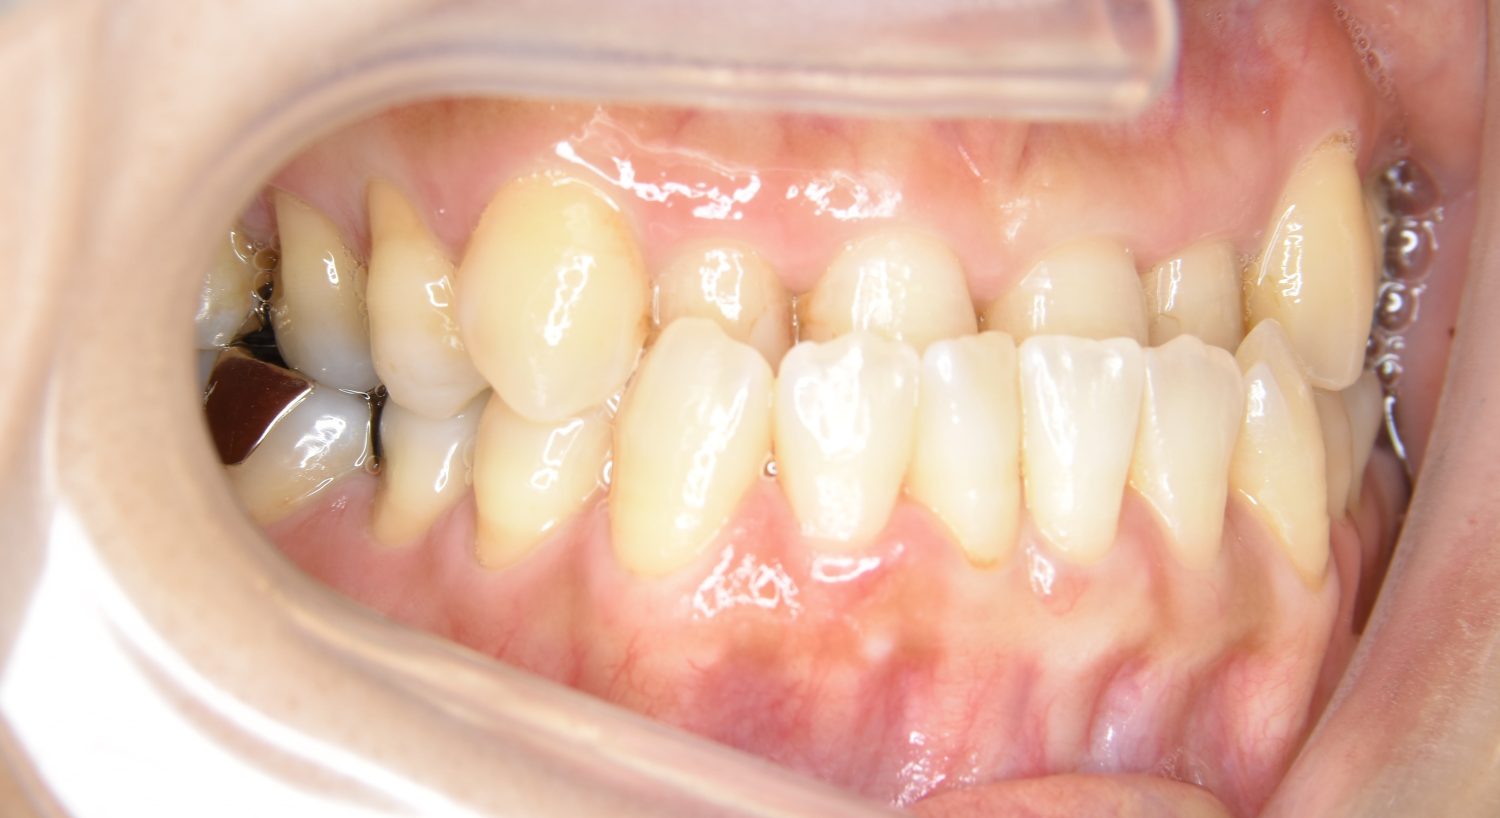

叢生の症例紹介②

Before

主訴

歯の凸凹を治したい。

治療内容

アライナー(インビザライン)にて非抜歯で治療を行いました。

治療費

1,150,000 円(税込)

治療期間

26ヶ月

通院回数

14回

想定されたリスク

※歯根吸収、歯肉退縮、歯髄壊死、顎関節症状

※アライナー(インビザライン)は日本の薬機法未承認の矯正装置であり、医薬品副作用被害救済制度の対象外となる場合があります。

上下前歯部に叢生(凸凹)が認められる状態でした。歯列の遠心移動を行うことで機能面および審美面が改善されました。